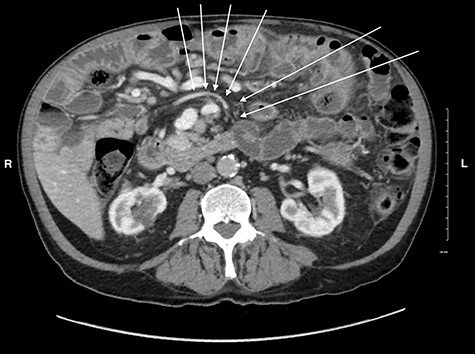

Midgut volvulus is an uncommon disease most often presenting in children, with rare occurrences in adults [3]. It is characterized by an abnormal rotation of the intestine around a fixed-point. Associated congenital conditions include gastrointestinal malrotation, jejunoileal diverticulosis and a history of abdominal wall defects [5, 6]. Acutely, volvulus can be intermittent or complete, with variable symptoms, leading to obstruction, bowel necrosis and possibly death. Chronic presentations of midgut volvulus can also occur, resulting in recurrent pain, intermittent obstruction and malabsorption over months to years. Due to its rarity in adults and variable presentation, preoperative diagnosis of intestinal volvulus is challenging. Adding to this difficulty, a classic ‘whirlpool sign’ or abnormal superior mesenteric vessel configuration is only present on CT in 30.9 and 58% of cases, respectively [3]. Retrospectively, the right-sided position of the duodenojejunal flexure and slight swirling of small bowel mesentery is visible but clouded by numerous jejunoileal diverticula (Figs 5 and 6).

CT image of the right sided position of duodenojejunal flexure, entering the intraperitoneal cavity on the right side of the abdomen.

CT image showing a subtle swirl of the mesenteric vein, coursing from the left to the right side of the abdomen indicating volvulus of the small bowel.